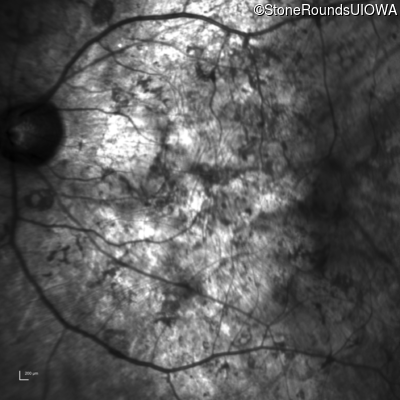

Optical Coherence Tomography - Left - Hand Motion

Exemplar / OCT Stack